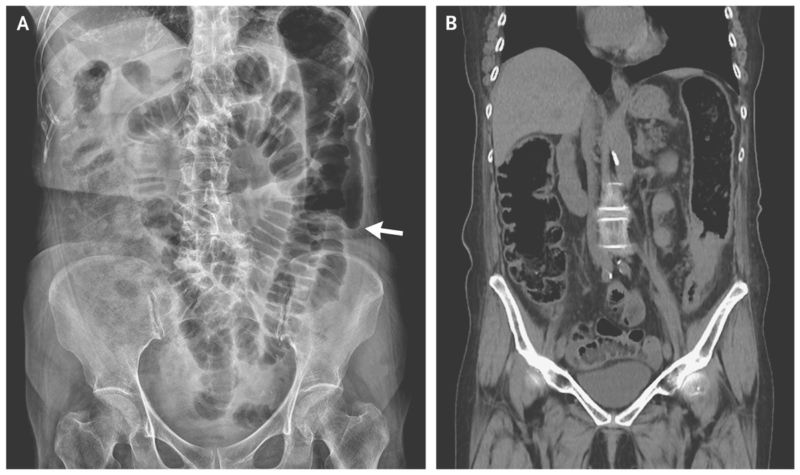

A plain-film radiograph of the abdomen showed marked dilatation of bowel loops and abrupt termination of gas within the descending colon, referred to as a colon cutoff sign (Panel A, arrow).

Computed tomography of the abdomen revealed segmental wall thickening of the descending colon (Panel B).

Colonoscopy revealed a circumferential ulcerative lesion in the descending colon, and the results of pathological testing were consistent with adenocarcinoma of the colon. In this patient, the colon cutoff sign was caused by mechanical narrowing due to colon cancer.